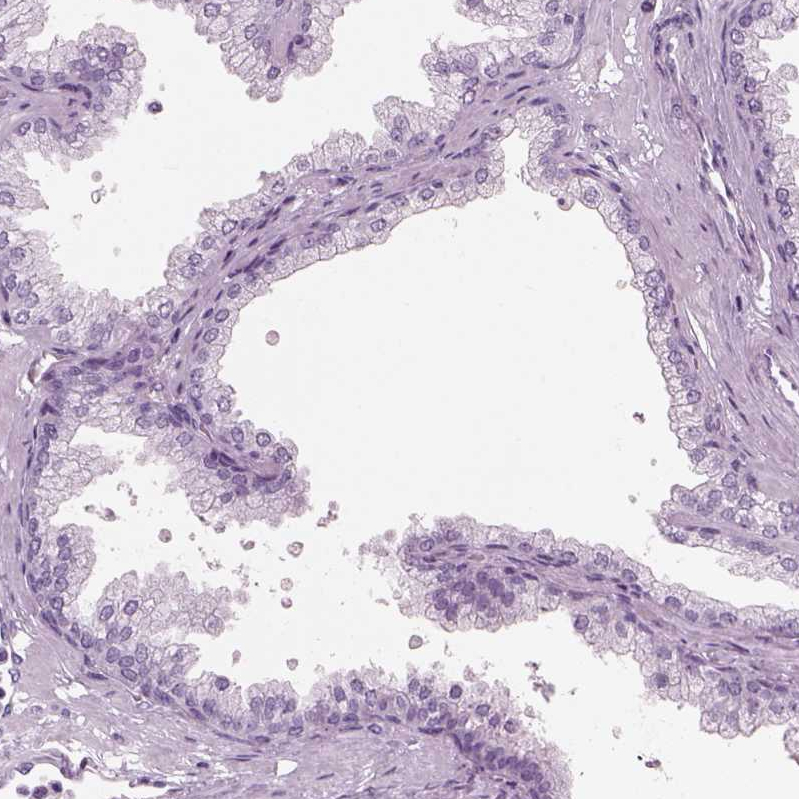

Immunohistochemistry analysis in human fallopian tube and prostate tissues using HPA067155 antibody. Corresponding HYDIN RNA-seq data are presented for the same tissues.